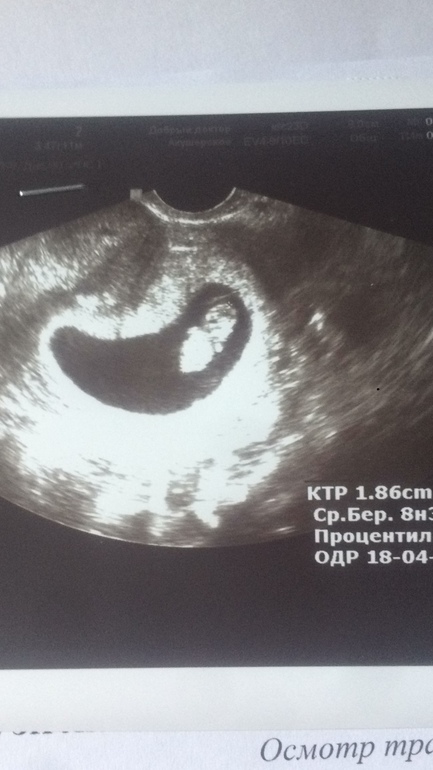

Мы встали на учёт, первый скрининг после 1 октября. А я никак не могла так долго ждать)) на работе ношусь, все меня бесит, все бесят, до слёз...поначиталась про ЗБ ещё, давай че-то переживать, хотя ничего не беспокоит (ттт) Хотя токсикоз был две недели и прошёл как-то резко, сейчас легонько мутит, если голодная. В общем, пошла я на узи, успокоилась) Всё у нас хорошо, сердечко ритмичное, срок совпадает (8 и 3), ручки, ножки есть) Боже, как это мило ❤️